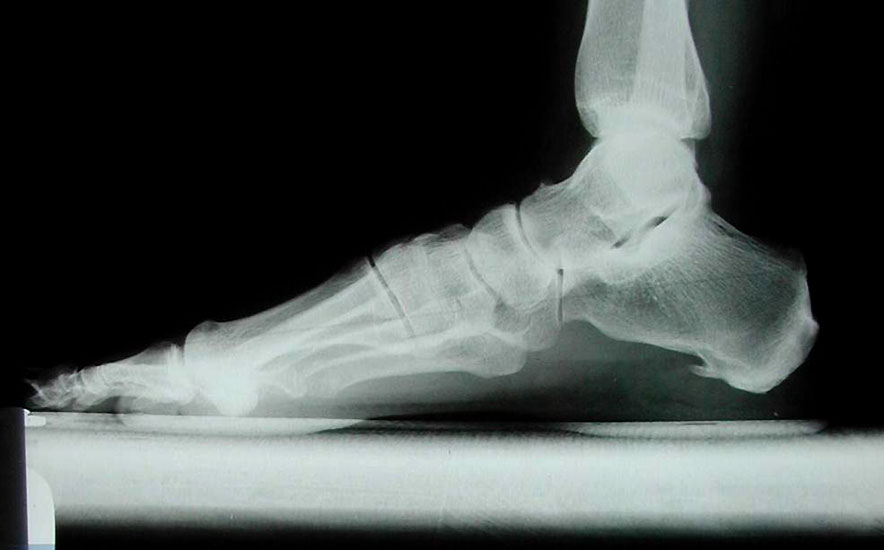

Im seitlichen Röntgenbild werden dorsale Osteophyten des Großzehengrundgelenkes als Ausdruck arthrotischer Veränderungen des Grundgelenkes befundet, eine nach dorsal gewinkelte Stellung der Oberkante des Metatarsale I im Verhältnis zum Metatarsale II deutet auf eine Elevatusposition des 1. Strahles hin (Abb. 7). Gelegentlich kann im seitlichen Röntgenbild ein plantares Klaffen des TMT I als Ausdruck einer Instabilität zu sehen sein (Abb. 8). Parallel verlaufende Metatarsalia I und II sind jedoch keinesfalls ein sicherer Beweis für das Fehlen einer Insuffizienz des 1. Strahles, da die Stellung der beiden Metatarsalia zueinander durch Rückfuß-Valgusdeformitäten fehlprojiziert sein kann.